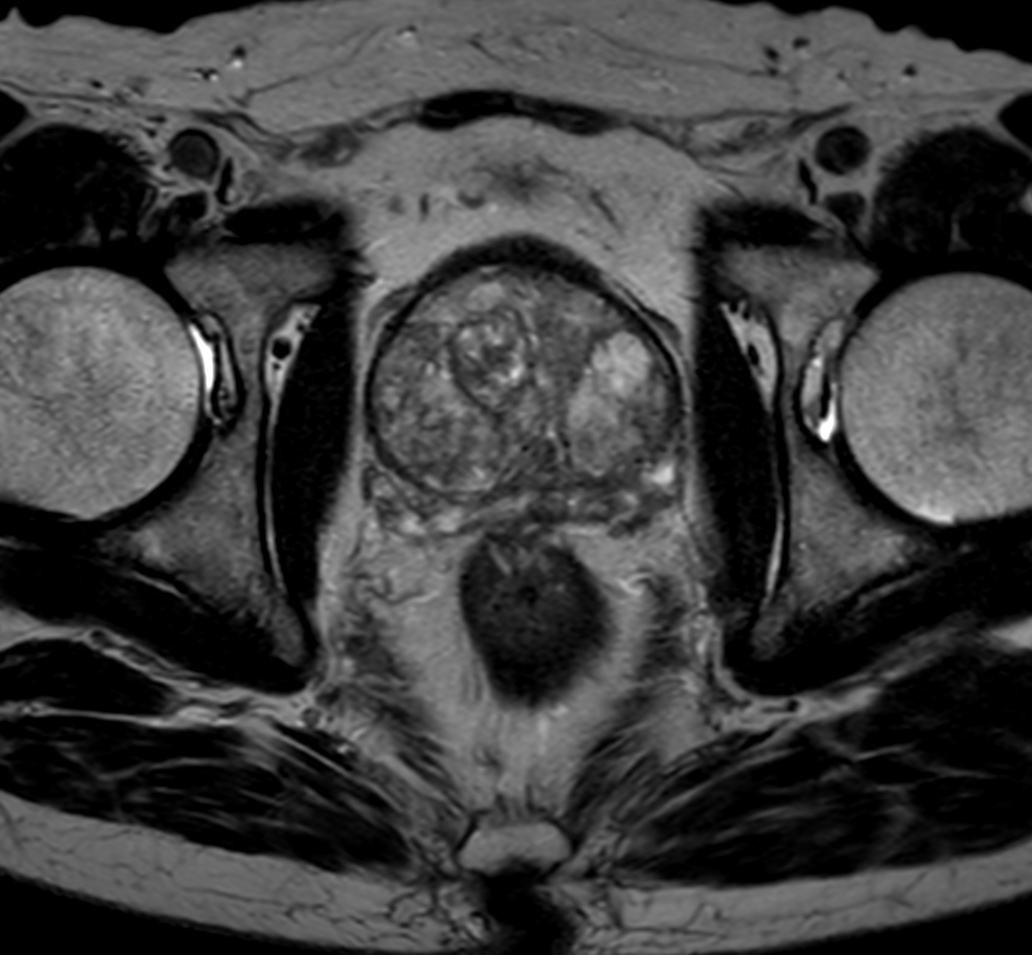

Multi-phase, contrast-enhanced prostate imaging

Patient with a prostate lesion. The ExamCard includes techniques for 3D imaging (PelvisVIEW, eTHRIVE) allowing for multiple image directions in one single scan, efficient fat-free imaging over large field-of-views (mDIXON XD), a multi-phase contrast-enhanced sequence (4D FreeBreathing) to improve imaging confidence and Compressed SENSE to accelerate the entire exam.

T2w TSE

T2w TSE Compressed SENSE